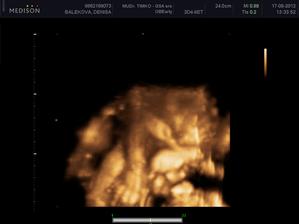

Nas anjelik Alex

Zatial este schovany v brusku ale uz coskoro sa z neho potesime aj nazivo 🙂) Lubime nasho Alexa uz od sameho zaciatku 🙂